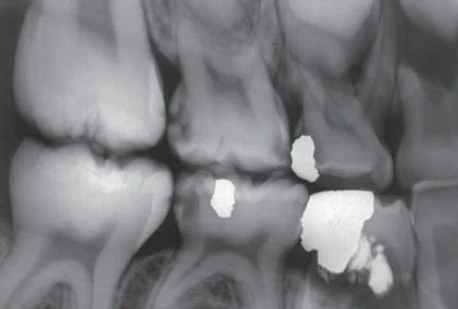

Khám kĩ càng hơn trên răng thấy một điểm gợi ý ở mặt nhai phía xa của răng. Dưới kính lúp và chiếu đèn có thể thấy một đường nứt nhỏ ở gờ viền phía xa (Hình 3). Thử giấy cắn cho thấy vị trí này chạm nhiều.

Hình 3: Đường nứt nhỏ ở gờ viền phía xa.